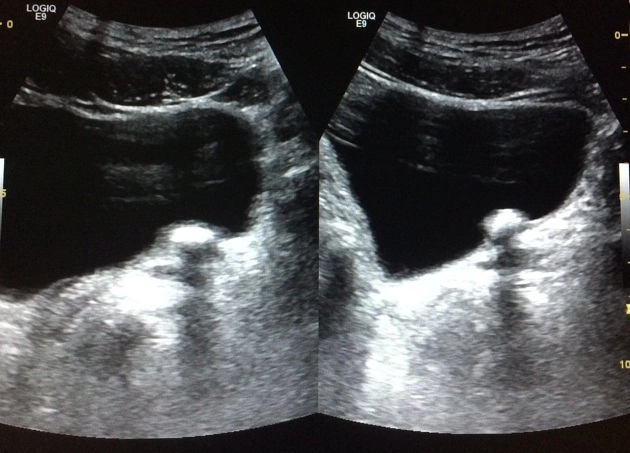

Sỏi niệu quản (Ureteric calculi)